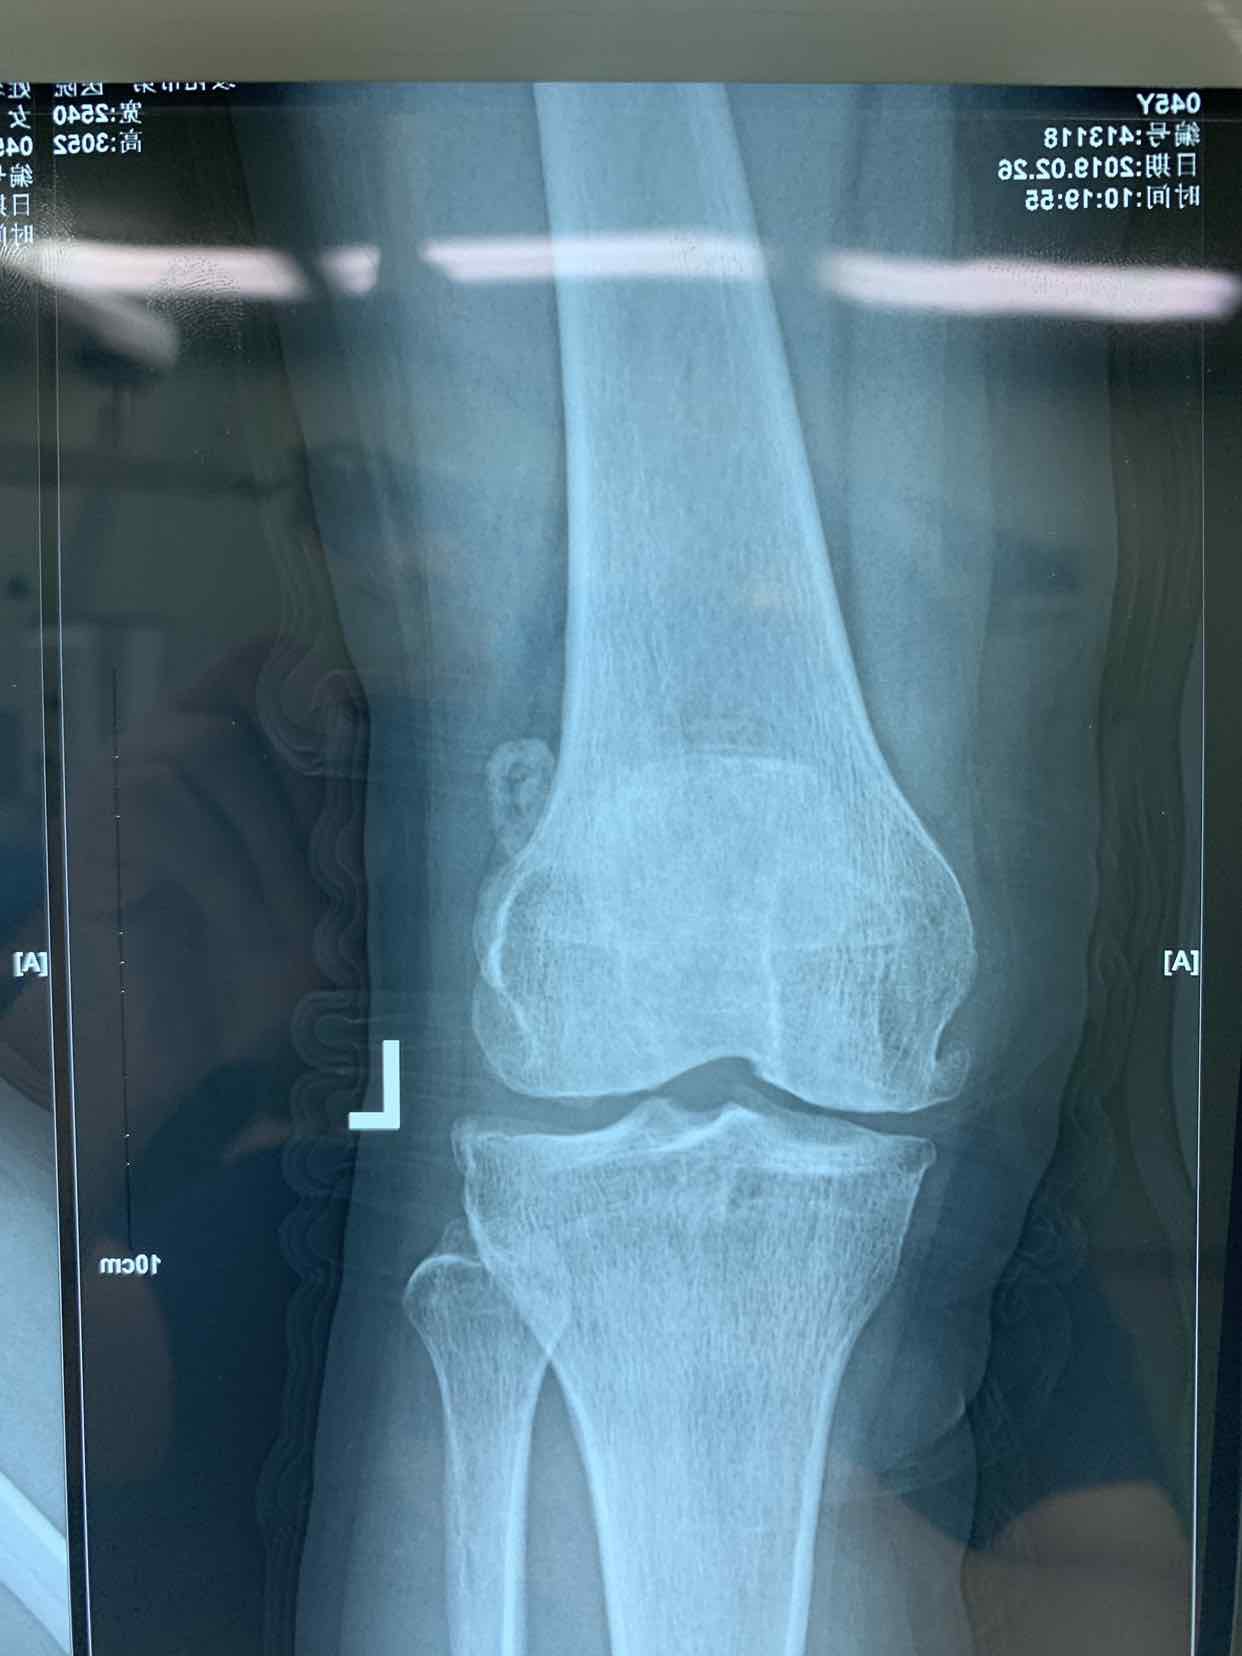

患者因双侧膝关节骨性肿物发现二十余年。收入院。患者无二十余年前无明显诱因发现双侧膝关节内有骨性肿物。异常活动。偶尔在屈曲活动时出现局部嵌夹于关节内。疼痛。不能活动。并弹响。近半年内肿物增大。疼痛发作频繁。遂来诊。门诊拍片提示见双侧膝关节内骨性游离体,位于关节内。门诊以双侧膝关节游离体收入院。

查体见患者双侧膝关节局部肿胀。压痛。可于局部触及骨性肿物在关节内游走。屈伸活动时偶有嵌顿。行走活动受限。拍片提示双侧膝关节骨性游离体。

诊断为双侧膝关节游离体。再局麻下银行膝部游离体取出术。术后患者恢复良好。

膝关节游离体是临床常见疾病。可以通过关节镜探查发作。拍片或者核磁共振检查也可获得可靠诊断。处理非常简单。发现肿物挤压至一侧。切口就可以取出。